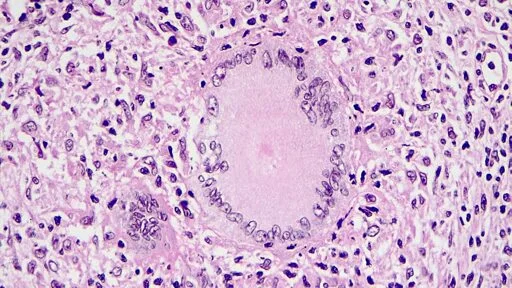

Kansas faces one of the largest tuberculosis outbreaks in US history